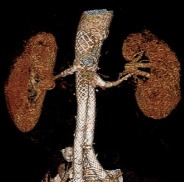

Ultra-Low Profile FEVAR-Implantat

Optionen für eine doppelte oder einfache Fenestrierung sind erhältlich, mit oder ohne Ausschnitt (Scallop) an der oberen Eingeweidearterie. Fenestrierte Iliakal-Komponenten sind ebenfalls erhältlich.

Zusätzlicher Nutzen für das endovaskuläre Instrumentarium